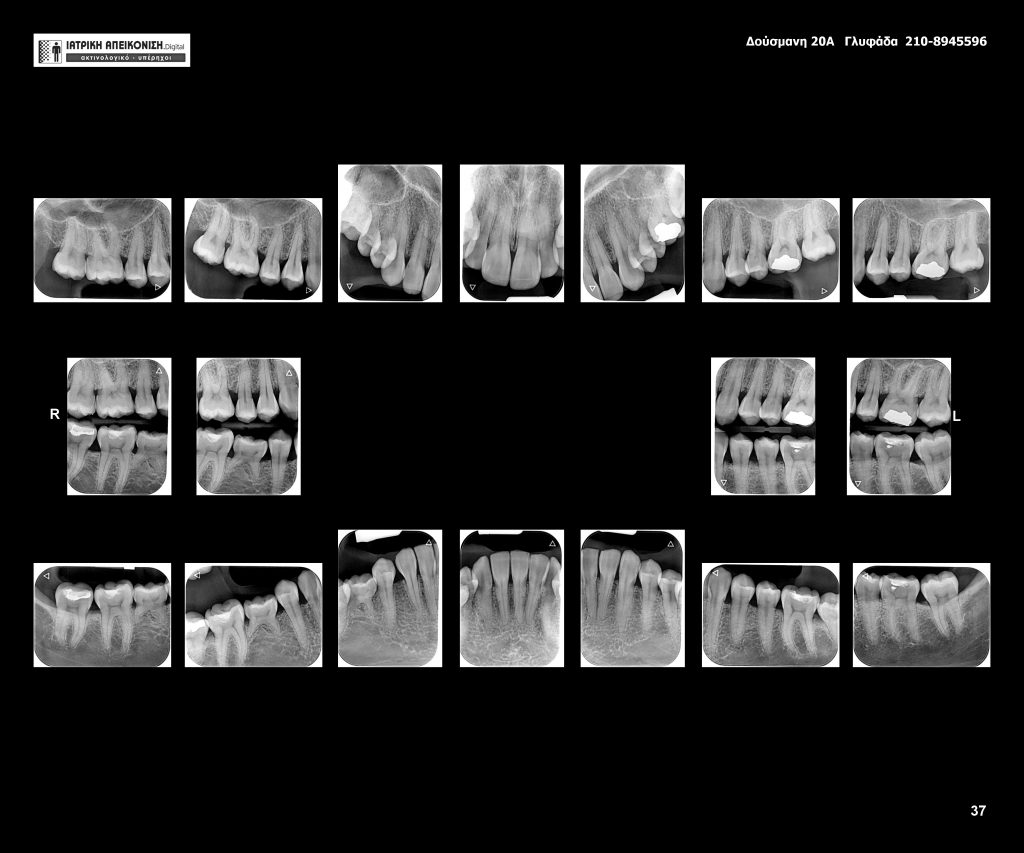

Στο τμήμα αυτό διεξάγονται ψηφιακές πανοραμικές, κεφαλομετρικές, πλήρης σειρά οπισθοφατνιακών ακτινογραφιών (full-mouth), δήξεως CBCT-3D Dental Scan, απεικονιστικός έλεγχος ΕΝΤ/ΩΡΛ και 4D κινησιογραφία της γνάθου σε πραγματικό χρόνο. Στόχος μας είναι να παρέχουμε την καλύτερη οδοντιατρική και γναθοπροσωπική ακτινοδιάγνωση.